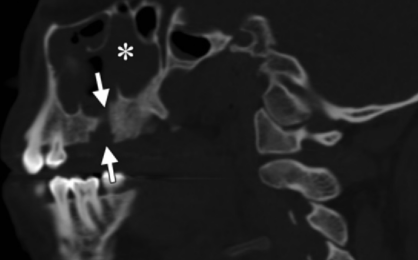

Fistule orosinusienne

- Après extraction dentaire ++

- Se ferme spontanément jusqu’à 2 mm

- Sinon forme une fistule

- Cliniquement : bulles sortant autour de la dent quand on gonfle le nez

- Souvent epaississement muqueux et comblements du sinus maxillaire

Sinusite odontogène

- Vient d’une maladie péri-apicale ++

- Bacteries différente que les autres sinusites

- Visualisation d’une dent avec une carie et une périodontite apicale

Sinusite + périodontite apicale avec dent cariée = suspicion